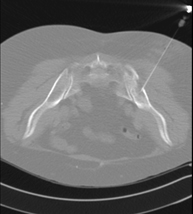

- Biopsia ósea guiada por TC

Consiste en obtener una muestra de tejido de una determinada lesión ósea. En ocasiones se realiza bajo sedación, con la ayuda del equipo de anestesia. Se utilizan agujas que permiten la obtención de un cilindro de la lesión a estudiar, que se enviará a Anatomía Patológica para su análisis histológico. Todo el procedimiento se realiza controlado con imágenes obtenidas por Tomografía Computarizada (TC) en varios momentos de la biopsia, mediante el empleo de Fluoroscopia-TC. Tras la prueba, el paciente permanece hospitalizado para controlar su evolución. Es necesario aportar pruebas de coagulación antes de la punción.